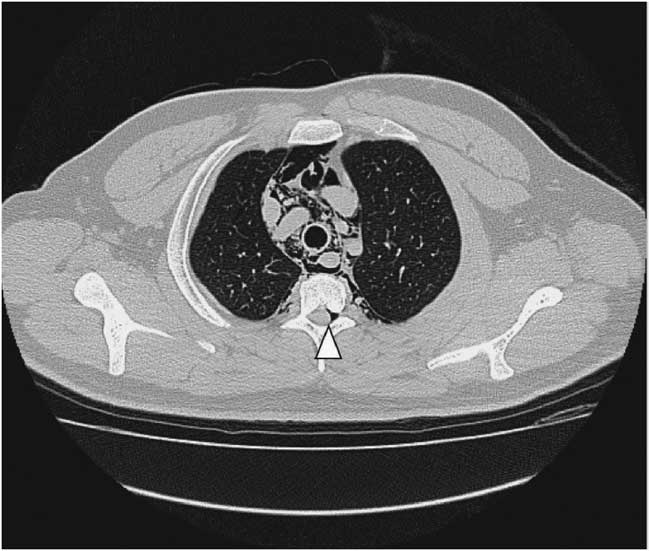

A 22-year-old male presented to the emergency department due to progressive odynophagia and dysphagia. He underwent a left third mandibular molar extraction at the dental clinic a week prior. At the emergency department, vital signs were normal except tachycardia (114/min) and tachypnea (22/min). A physical examination revealed bilateral neck tenderness with crepitus on palpation, no stridor or acute airway compromise signs. Laboratory data showed leukocytosis (white blood cell count, 19000/cumm; segmented, 91%) and elevated C-reactive protein (1.07 mg/dL). Radiographs showed the presence of prevertebral emphysema on the C-spine lateral view (Figure 1) and subcutaneous emphysema with pneumomediastinum on the chest posteroanterior view (Figure 2). A non-contrast computed tomography (CT) scan confirmed the radiographic findings; additionally, there was gas collection over the pericarotid, pericardial (Figure 3) and extradural spaces (Figure 4). Because there was no CT evidence of infectious signs and clinical features were stable, conservative treatment with intravenous amoxicillin/clavulanic acid was given for a week. Clinical symptoms improved, and a follow-up CT showed no residual gas.

Figure 4 Non-contrast chest computed tomography shows gas collection at thoracic extradural space: pneumorrhachis (arrowhead).

Although subcutaneous emphysema is a rare complication following dental procedures, with mostly benign and self-limiting sequelae, it may progress to fatal consequences such as cardiac tamponade, air embolism, pneumothorax, and mediastinitis.Reference Goodnight, Sercarz and Wang 1 There have been reports correlating subcutaneous emphysema and dental treatments with the use of air turbine hand-pieces and air syringes.Reference McKenzie and Rosenberg 2 , Reference Arai, Aoki and Yamazaki 3 CT is useful to detect the precise extension of gas dissection, such as pneumomediastinum, pneumopericardium, and pneumorrhachis, in this case.Reference Ehmann, Paziana and Stolbach 4 Most importantly, CT can evaluate the complications of extensive emphysema or infectious process. In addition, it can guide clinical treatment decisions like the need for urgent tracheostomy or fasciotomy.